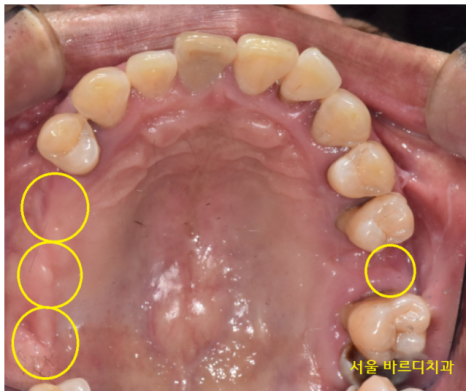

231218

그동안 치아 상태는 이런 모습이셨어요.

어금니라고는 단 2개 만 남아있었습니다.

오른쪽 1개 왼쪽 1개

식사가 얼마나 어려우셨겠어요~

뭐라도 드셔야 하시니 임시틀니로

식사하실 수 있게 도와드렸습니다.